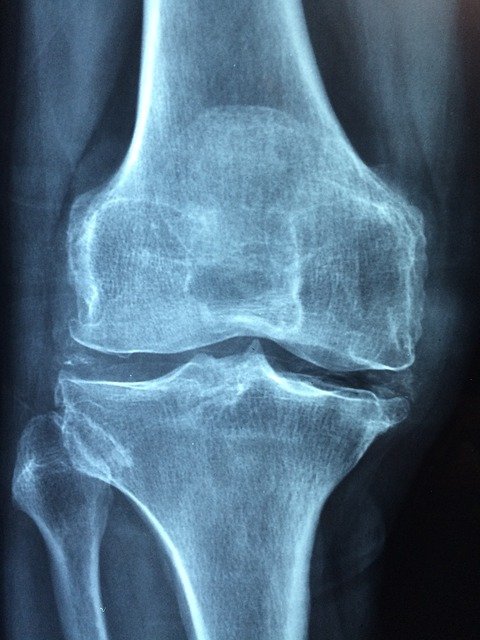

무릎 연골은 혈관도 없고 한번 손상되면 다시 생성되기 어려운 조직으로 무릎 연골 두께는 3mm 정도이며 무릎 등의 연골이 닳아 없어진 경우 무릎 통증을 많이 호소하게 되는데요.

연골은 안 좋아질 때까지 자각증상이 크지 않다가 무릎 통증이 느껴지면 이미 연골은 많이 손상된 상태로 치료하기가 쉽지 않으며 퇴행성관절염의 경우에는 거의 재생이 불가능합니다. 그래서 연골 그중에서도 하중을 제일 많이 받는 무릎 연골은 특히 미리미리 건강 관리를 해 주는 것이 필요합니다.